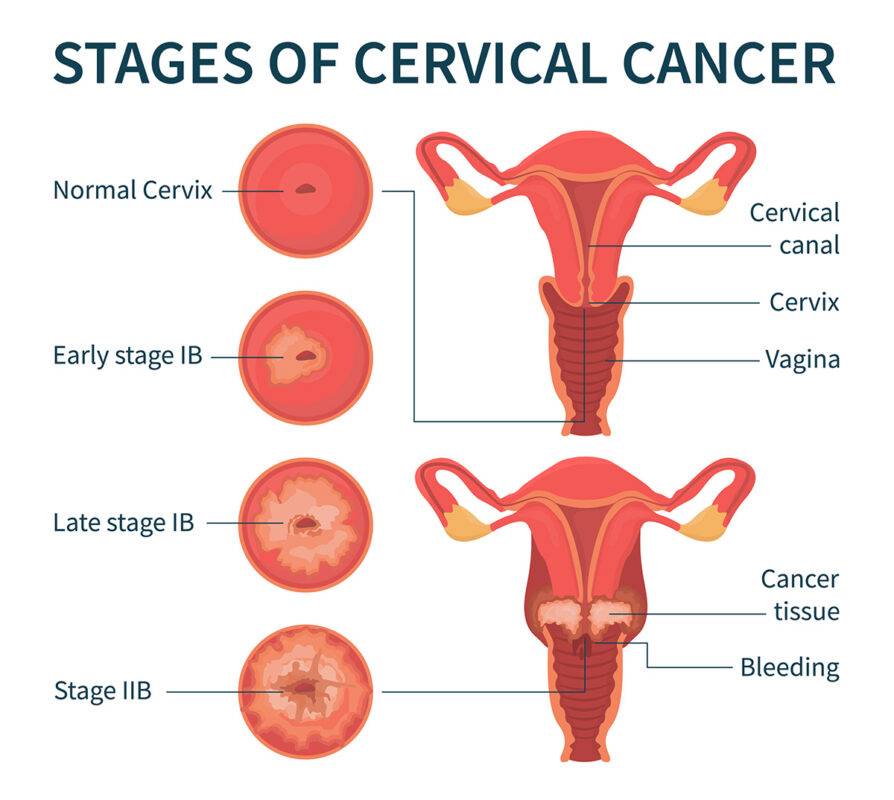

Cervical Cancer

Cervical cancer starts in the cells lining the cervix — the bottom part of the uterus (womb). The cervix connects the body of the uteru...